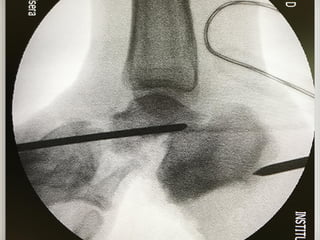

Diagnóstico

• Punción

• Tinción de Gram y cultivo

• leucocitos arriba de 50,000 mm3 (polimorfonucleares)

• Proteínas

• baja concentración de glucosa (menos 30% sérico.)